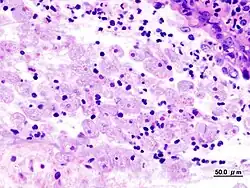

Von der kleineren „Minutaform“ der Trophozoiten, die nicht zum klinischen Bild der Amöbenruhr führt, ist die bis 50 Mikrometer große pathogene „Magnaform“ abzugrenzen, die Erythrozyten phagozytieren kann. Aus bisher unbekannten Gründen können sich die Erreger verändern und neben veränderter DNA ein verändertes Enzymmuster zeigen. Infolge verschiedener Pathogenitätsfaktoren wie bestimmter Oberflächenrezeptoren, porenbildender Enzyme sowie Zysteinproteasen, die die extrazelluläre Matrix des Colons zersetzen, kommt es zum Vollbild der Amöbenruhr. Dabei können in seltenen Fällen infolge einer chronischen granulomatösen Entzündungsreaktion druckempfindliche Geschwulste in der Darmwand entstehen, ein sogenanntes Amöbom.[2]

Diese intestinalen Symptome sind Zeichen einer invasiven Amöbiasis, bei der Trophozoiten aus dem Darmlumen in die Schleimhaut des Dickdarms übertreten. Hierdurch kommt es zu einer Entzündung des Dickdarms (Colitis), die mit umschriebenen Gewebsdefekten geschwürig ist (Ulzerationen). Wenn die Amöben über die Darmschleimhaut in das Gefäßsystem eindringen, können sie mit dem Blut weiter transportiert werden. Damit können sich außerhalb des Darms (extraintestinale) Absiedlungen von Amöben in anderen Organen bilden und dort anschließend Abszesse. Leberabszesse sind hier die weitaus häufigste Komplikation, das Zentralnervensystem, Herz, Milz oder Harnorgane sind selten betroffen. Diese extraintestinalen Manifestationen einer invasiven Amöbiasis können auch ohne vorausgehende Amöbenruhr auftreten, manchmal Jahre nach einer Infektion, und sind lebensbedrohlich.[2]